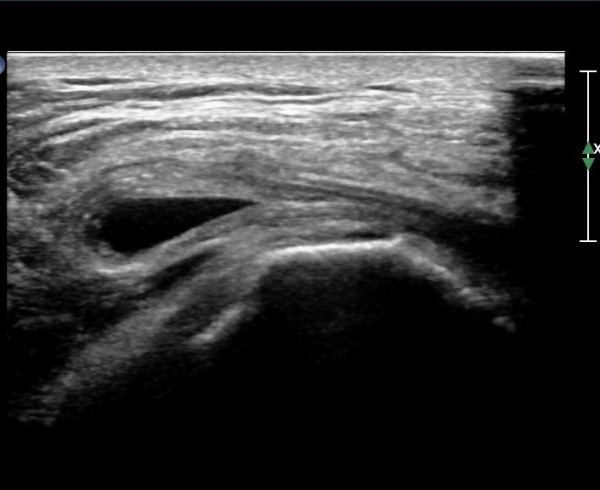

´ëÀüÀÚ µÚÂÊ È¾´Ü¸é°Ë»ç¿¡¼­ ÁߵбÙÈûÁÙ°ú Àå°æÀÎ´ë »çÀÌ¿¡ ·®ÀÇ ¼ö¾×Àú·ù°¡ °üÂûµÇ°í(»çÁø 1)